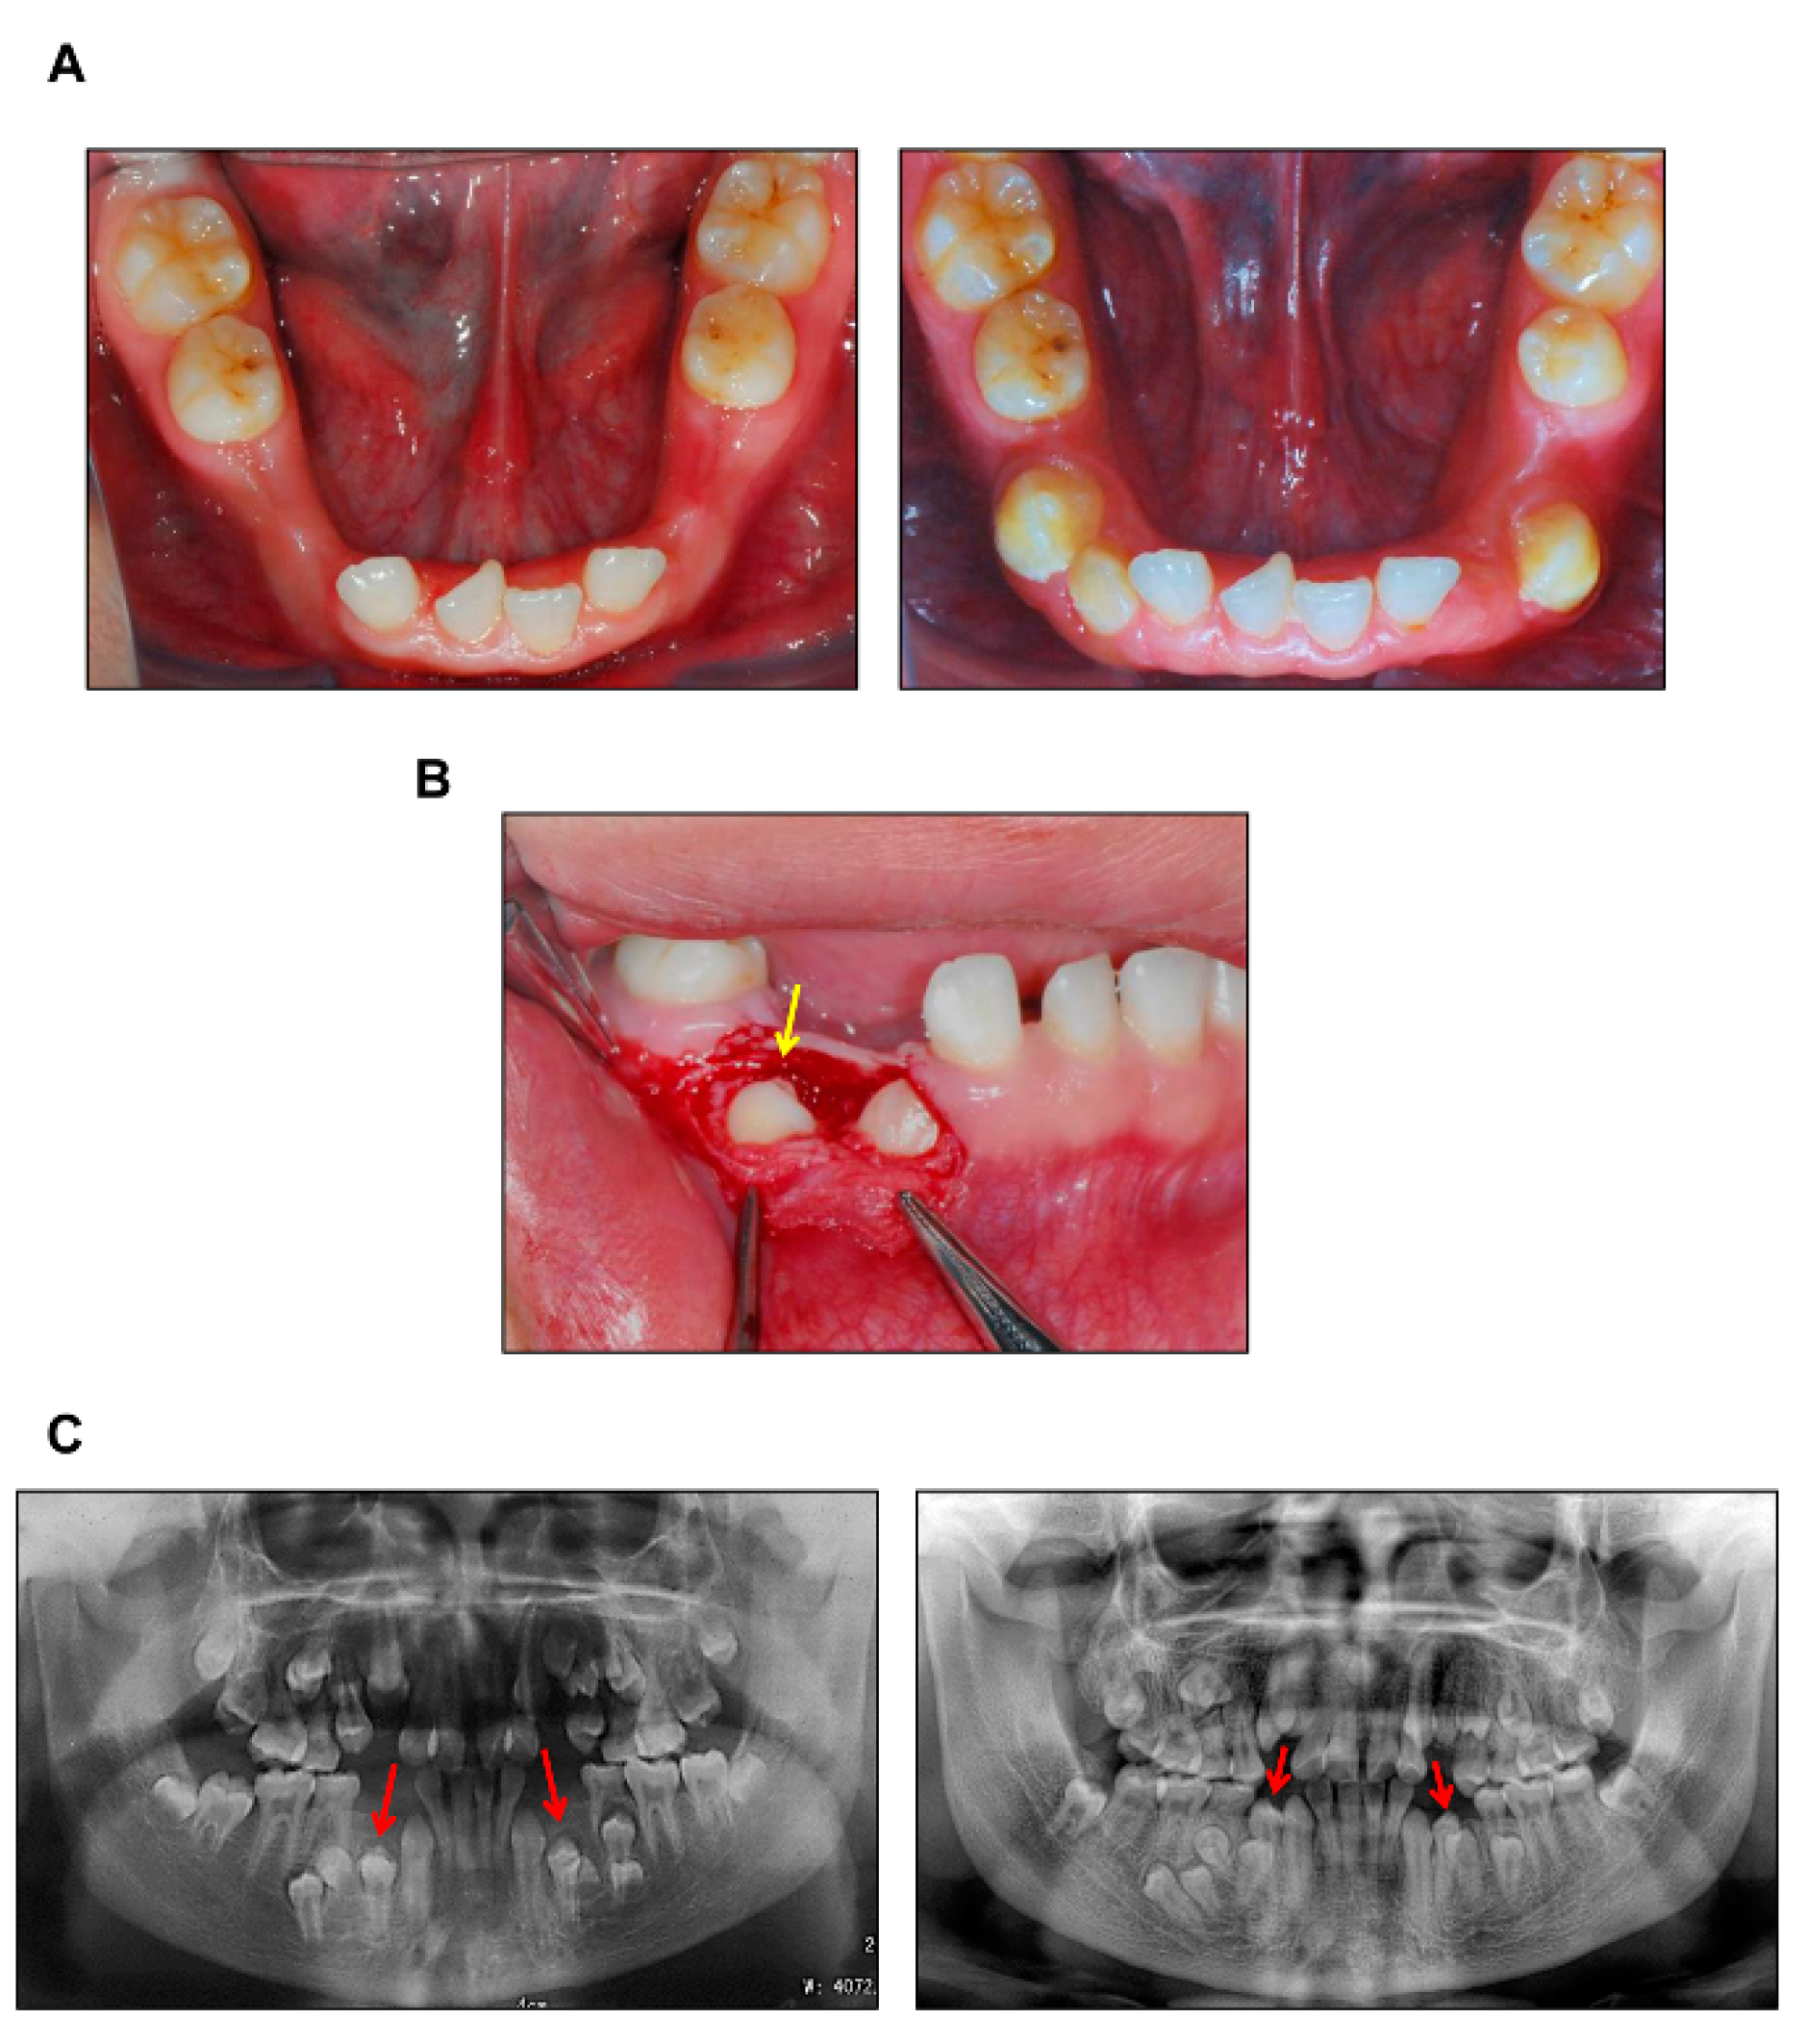

3.1. Delayed Eruption of Permanent Teeth in CCD Primarily Results from Deficient Alveolar Bone Resorption